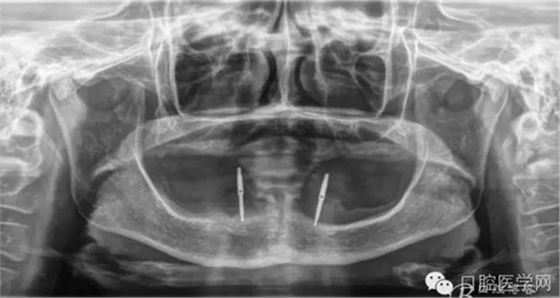

種植覆蓋全口義齒X線顯示骨量條件可以,準(zhǔn)備從下頜兩側(cè)大概3、4的位置植入植體。

種植覆蓋全口義齒判斷位置。